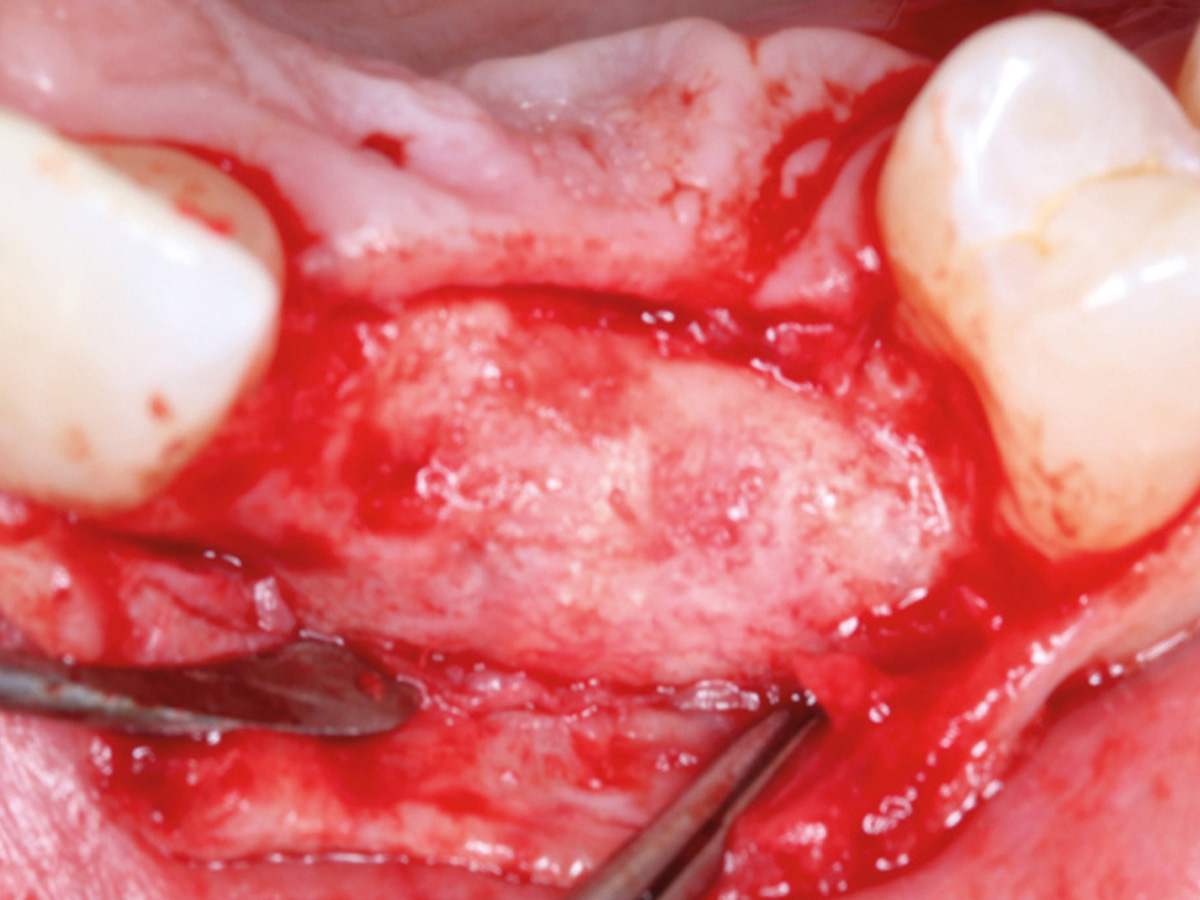

Abbildung 9

Retromolarer Eigenknochengewinn.

Abbildung 10

Eigenknochen mit OsteoBiol Apatos Mix.

Abbildung 11

Auffüllen des Defekts mit einem Gemisch aus Eigenknochen und OsteoBiol apatos Mix.